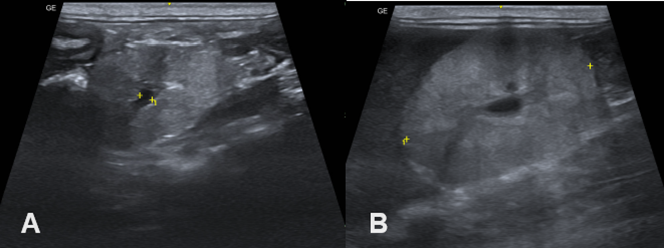

An abdominal ultrasound was performed which revealed reduced right and left kidneys, with loss of corticomedullary definition and coarse echotexture compatible with nephropathy indicative of renal dysplasia (Figure 2).

Figure 2 Abdominal ultrasound. A. Left kidney. B. Right kidney. Both kidneys showed a decrease in size, but there was a marked loss of corticomedullary relationship and coarse echotexture in the left kidney.

The diagnosis of renal dysplasia is based on anamnesis, clinical signs, laboratory findings, diagnostic imaging and histopathology. In the blood count, non-regenerative anemia is often observed due to low renal production of erythropoietin,2 which is in agreement with this case report. With Hyperphosphatemia and hypocalcemia can also be observed, which can lead to the emergence of secondary renal hyperparathyroidism.10 In our case report, a small increase in serum phosphorus levels was observed. By measuring urea and creatinine levels, and creatinine protein ratio, it was possible to confirm renal failure, in accordance with the literature.2–4 In urinalysis, the presence or absence of proteins are described in the literature, while isosthenuria11–13 is a commonly described finding and is in agreement with our results, along with the presence of E. coli in the urine. The abdominal ultrasound examination is essential in detecting changes compatible with renal dysplasia, where the kidneys have reduced dimensions, loss of the corticomedullary relationship, and increased echotexture,2,14 fact described in our case report.